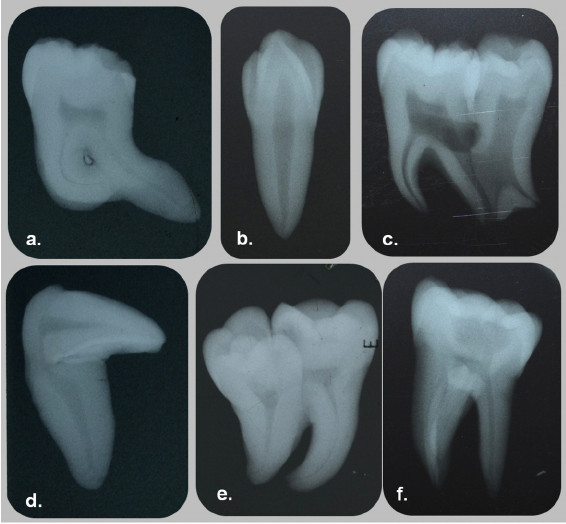

Ectopic position constitutes the second most common positional anomaly of the dentition. Within this category, the one that concerns clinicians the most is impaction. Even though any one tooth from either dental arch can be impacted, impaction of the maxillary permanent canine receives most attention. This is the case for numerous reasons, including the central role that the canine plays in the function of articulation and occlusion. A second, nearly equally important reason, is its role in facial esthetics.

A brief mention will be made of yet another positional anomaly of the canines: transmigration. Transmigration is exclusive of the mandibular perma- nent canine. In this anomaly, the canine from one side of the arch migrates through the bone and erupts on the opposite side of the arch. For instance, the right mandibular canine migrates through the sympheseal area and erupts into the arch in the place where the left canine usually erupts. This anomaly could present a complex clinical problem, because the clinician will be facing a situation where the canine from one side appears to be missing, while the opposite side may appear to have a supernumerary canine.15 Like so many dental problems, this last anomaly is best detected by radiographic examination. If detected early enough, its treatment may not be too difficult. This will reinforce the urging of a mature teacher to obtain and examine our patients’ records with care and attention to detail.